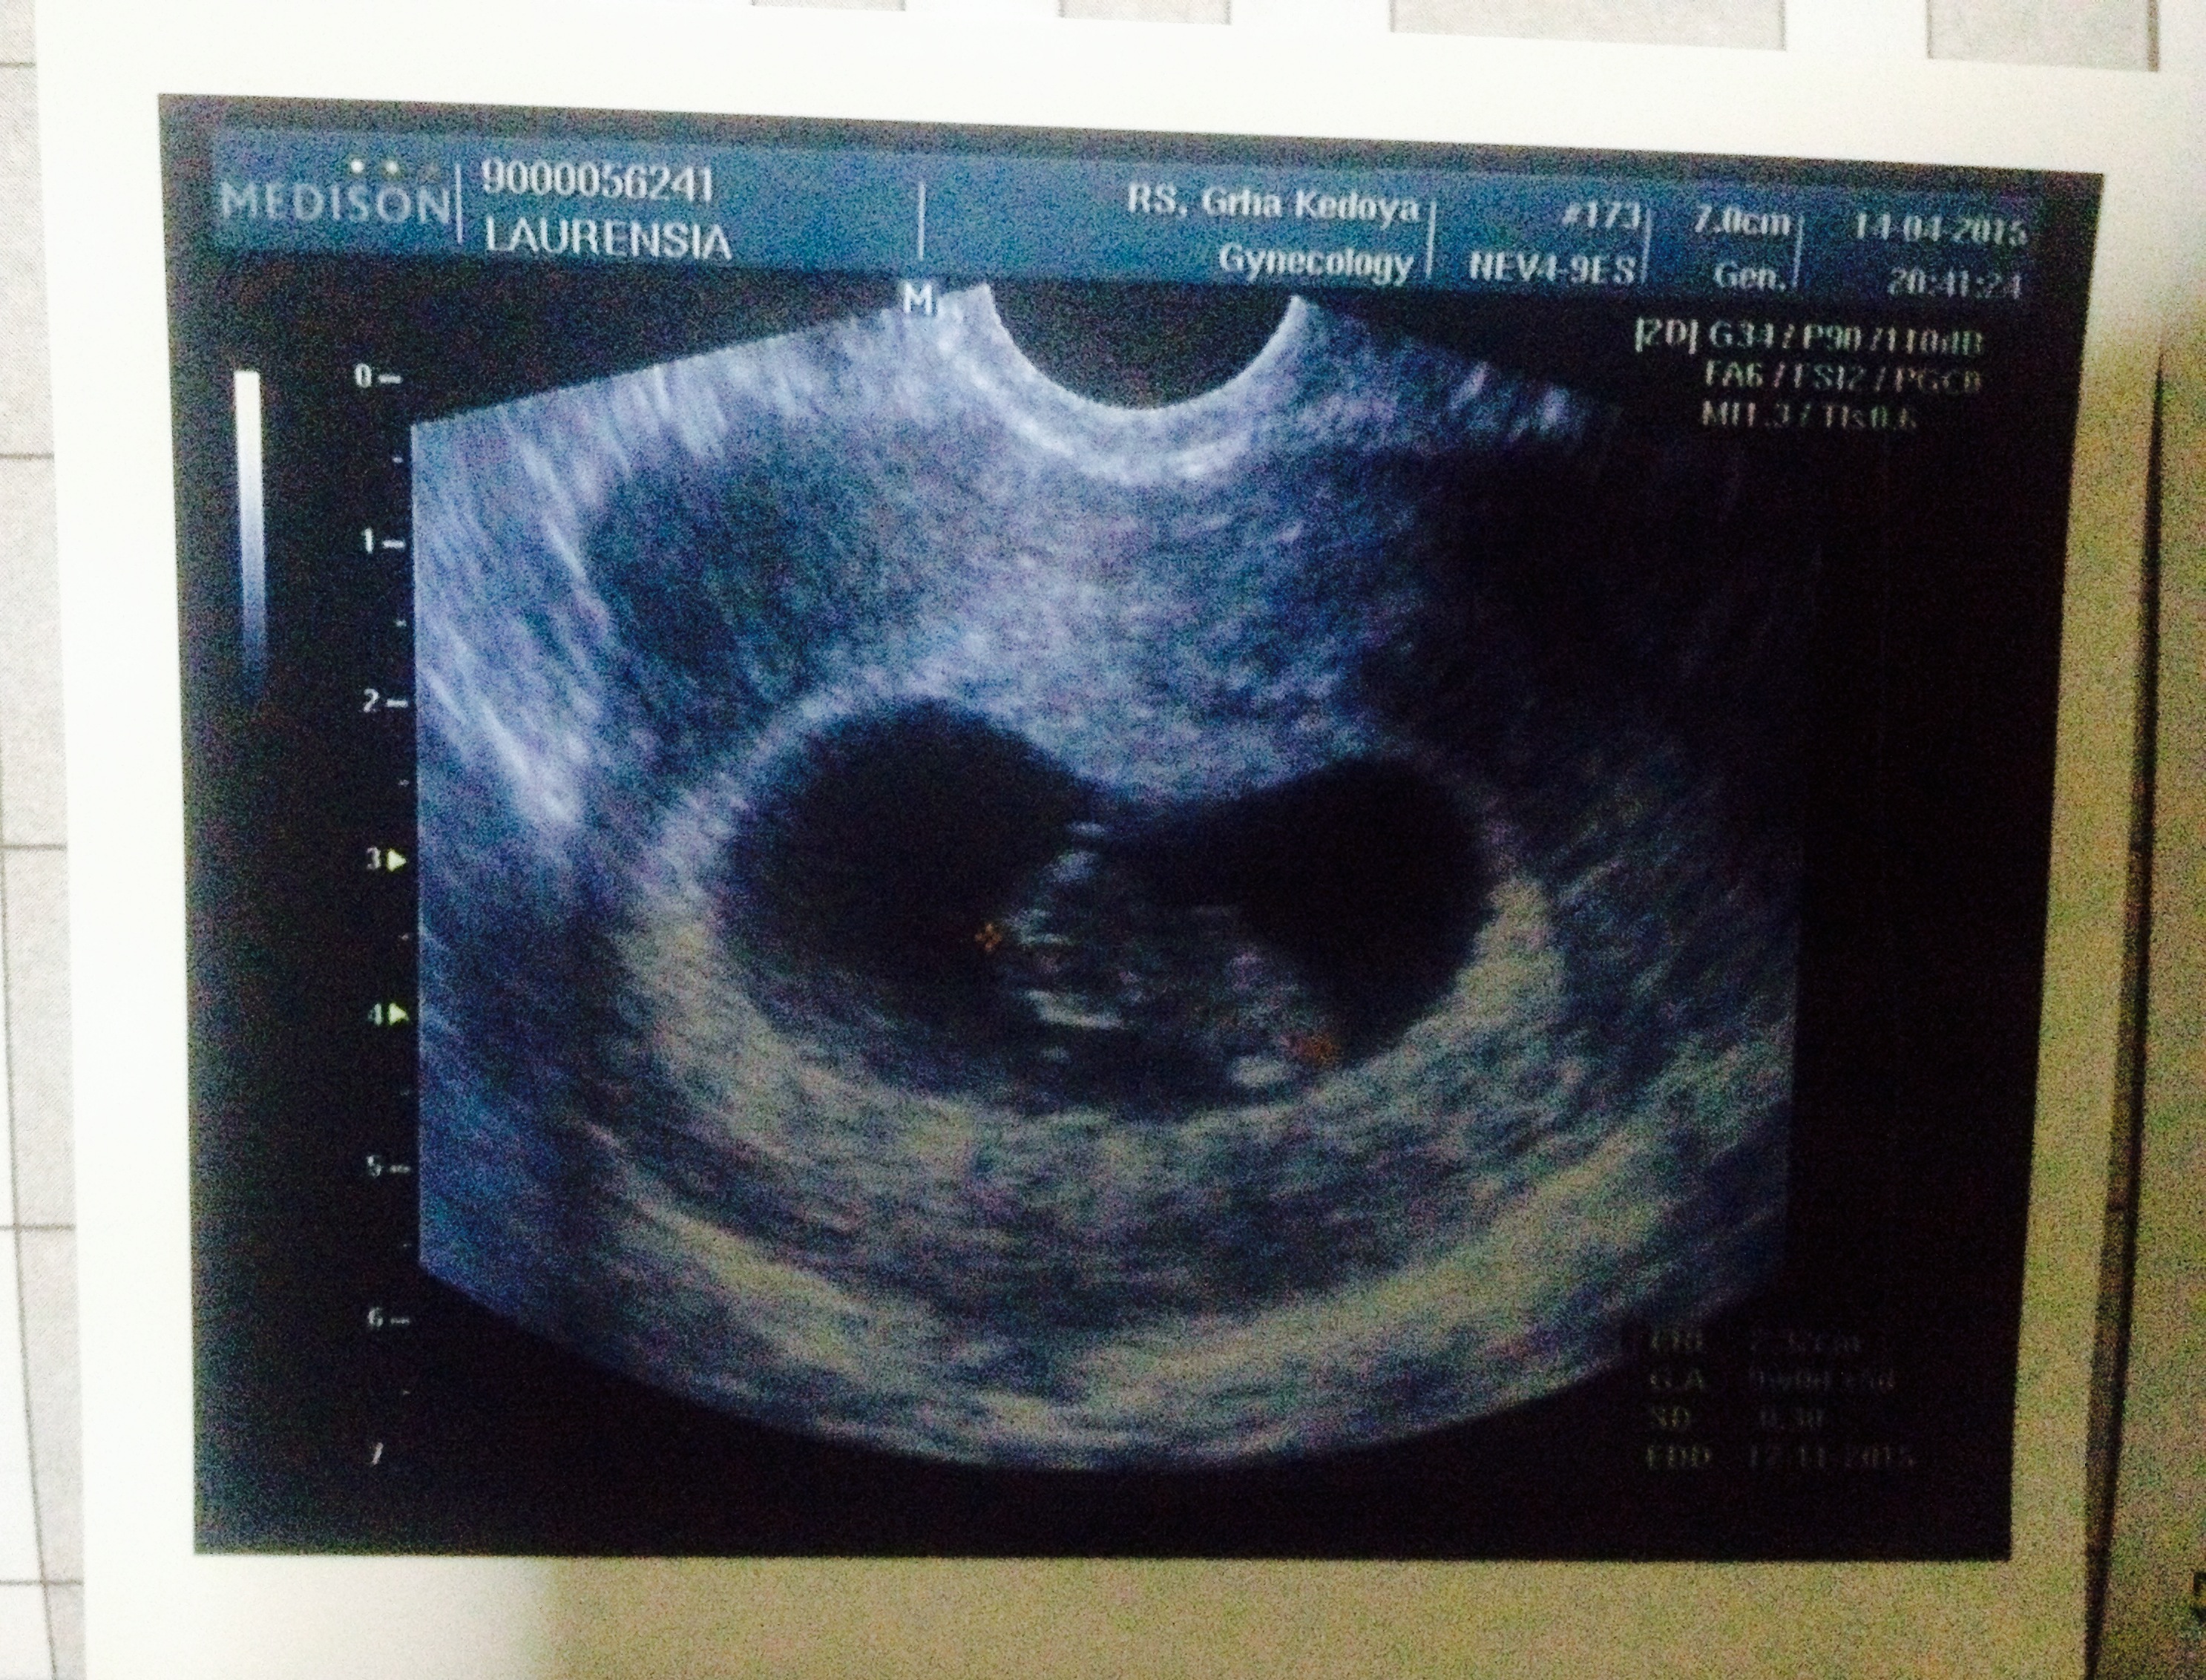

There was promise that I made for our family just a month ago , a promise to spread our happiness for our family, which is our little secret. This story belong to my wife and my son or daughter who are still in womb, not yet born, still young 2 months old.